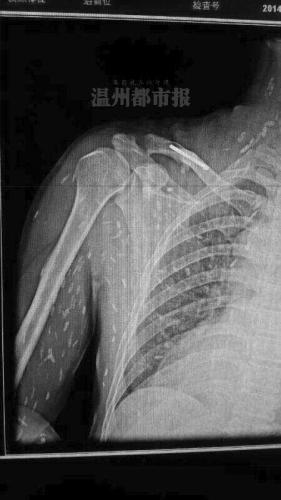

这两天,一张布满白点、看起来像长满寄生虫的图在网上热传。配图文字称:“瑞安一病人爱吃生鱼片,满身寄生虫?”

一位名为“doctor吴”的网友,在一论坛上发表了一篇《对微信流行的寄生虫一事个人见解》。文中,“doctor吴”表示,他从医学角度上对该片持怀疑态度。他认为,寄生虫的密度跟人体密度相仿,简单普通的X光并不能让它显影,CT下基本不能看到,除非聚集成团或者蛔虫。因为在胆道中,胆汁密度比虫体低,虫体密度与胆管相若,CT显影为胆道堵塞。

与此同时,他还提到,如果虫体死亡后钙化,那是可以在X光片中显影的。

这一说法得到我市寄生虫学专家认可。温州医科大学基础医学院副教授、寄生虫学教研室副主任黄慧聪认为,看到这样一张X光片,假如片子本身是真实的,通常会认为是寄生虫的软组织虫体广泛分布的皮下肌肉的钙化病灶。“通俗点说,就是寄生虫在体内死亡后钙化留下的斑点。”

黄慧聪指出,活的寄生虫是游走不定的,很难被X光片拍到,在直接影像学上是看不出来的。一般是形成虫囊或钙化后才容易被X光片观察到。但形成虫囊或钙化需要较长时间,通常要半年以上。如果像网上传的那样,由于食用生食短时间内出现这样的钙化灶,这种说法是值得怀疑的。

此外,他还说,出现图片所示那样广泛分布的钙化灶,通常考虑是旋毛虫病。这可能是生吃肉类导致,通过吃鱼感染的极为罕见。假如不是旋毛虫病,也可能是肺吸虫病。后者一般是通过生食溪蟹、蝲蛄(俗称小龙虾)等感染的,患病后虫体可能会游走,像图片里显示的这么密集,他还是第一次看到。

多位医学专业人士指出,单从这张X光片上看,图中白点如果真是寄生虫钙化后的显影,很像是囊尾蚴,这是扁形动物门绦虫纲幼虫的一种类型。

由于图片原始出处很难查找,这张令人毛骨悚然的X光片真伪难辨。相关人士分析指出,一者不能排除这张照片经过PS修改伪造的可能性,二者即使照片是真的,图中的白色斑点也有可能是患者体外衣物上或躯体表面的附着物。